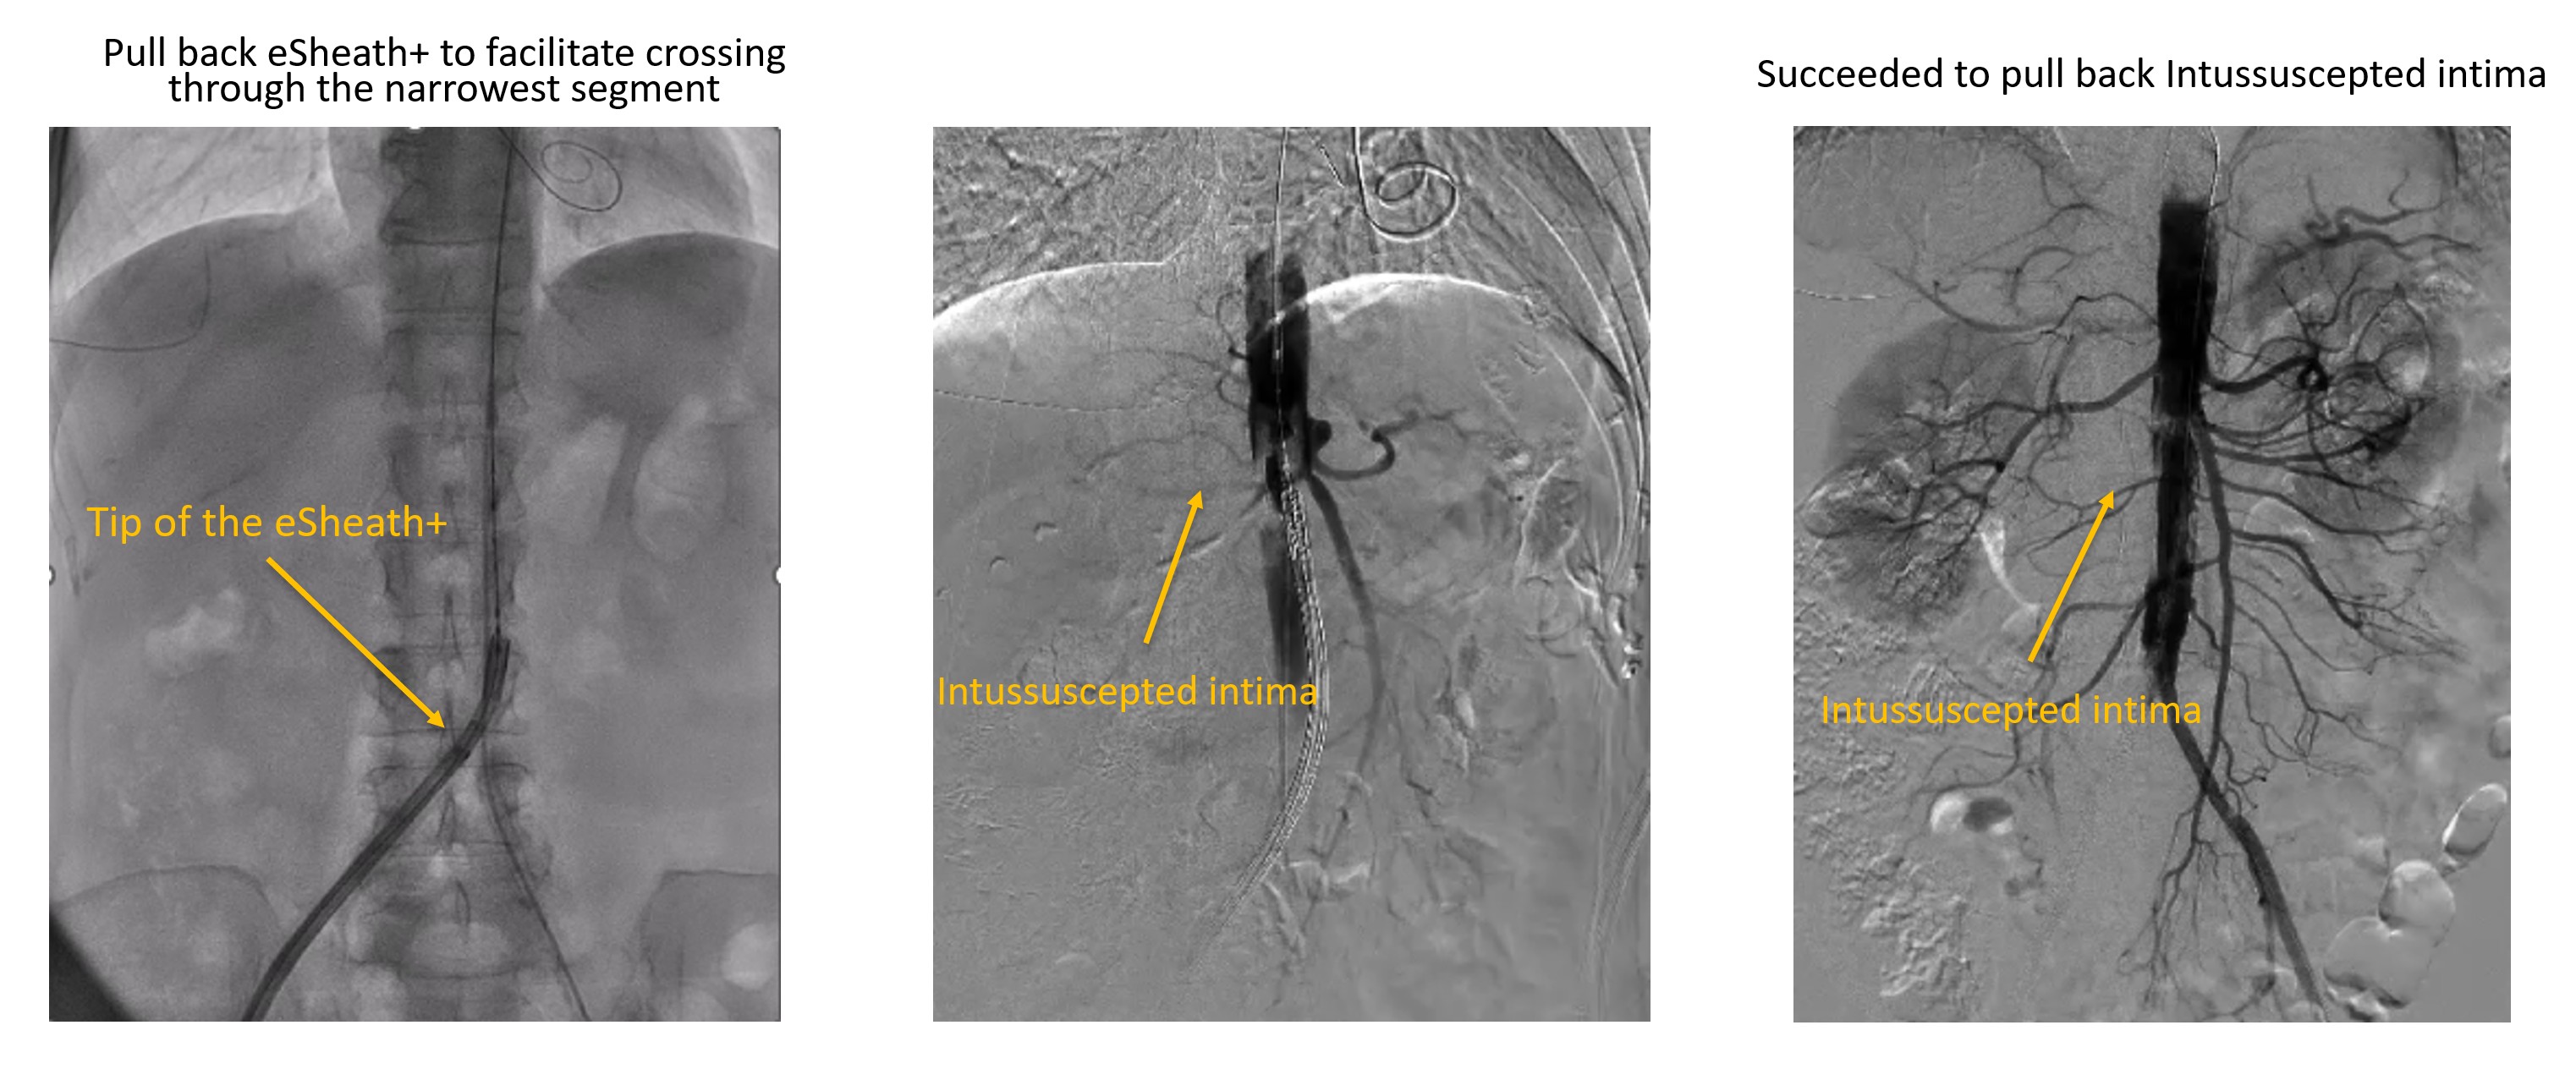

The procedure was performed under conscious sedation. A 14F eSheath+ was inserted via right femoral artery. The aortic valve was crossed using an AL 1.0 with an Argon straight wire, which was exchanged for SAFARI2 small. Although the diameter of iliofemoral artery was enough, delivery of SAPIEN 3 Ultra RESILIA 20 mm (S3UR) through the14F eSheath+ was challenging. The SAFARI2 wire was subsequently exchanged for a Confida Guidewire to get adequate support and back-up force; however, this also failed. Therefore, the 14F eSheath+ was pulled back to the common iliac artery, and the S3UR valve was advanced without the sheath to facilitate crossing through the narrowest segment of the iliofemoral artery. This maneuver succeeded to advance S3UR into abdominal aorta (Video 1). However, patient suddenly claimed severe abdominal pain and aortography revealed intimo-intimal intussusception, possibly caused during valve delivery (Video 2). Intravascular ultrasound (IVUS) also confirmed completely intussuscepted intima, and revealed absence of intimal layer at the terminal aorta. The TAVR procedure was subsequently aborted. The resultant tubular structure of completely detached intima posed a risk of antegrade or retrograde migration, potentially leading to acute aortic occlusion. Therefore, an endoprosthesis (GORE EXCLUDER) was implanted in the infrarenal aorta to stabilize the lesion (Video 3).